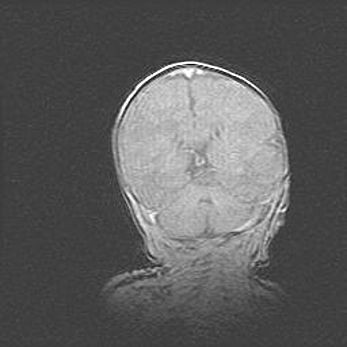

Множественные кисты обоих полушарий головного мозга, наибольшая из них в правой затылочной области. Ассиметричная атрофическая гидроцефалия.

Возраст: 7 месяцев

Вес: 5660 г

Пол: мужской

Окружность головы: 41,5 см

Срок гестации: 28-29 недель

Кисты головного мозга развиваются в результате многоочаговых некрозов вещества мозга и возникают вследствие перенесенной перинатальной инфекции, менингитов, энцефалитов, асфиксии, родовой травмы, расстройств мозгового кровообращения различного генеза. Образованию кист в веществе головного мозга плодов и новорожденных способствуют такие факторы, как высокое содержание в нем воды, недостаточная (или отсутствие) миелинизация и слабая астроглиальная реакция на повреждение.

Кисты могут сочетаться с гидроцефалией и другими поражениями головного мозга.